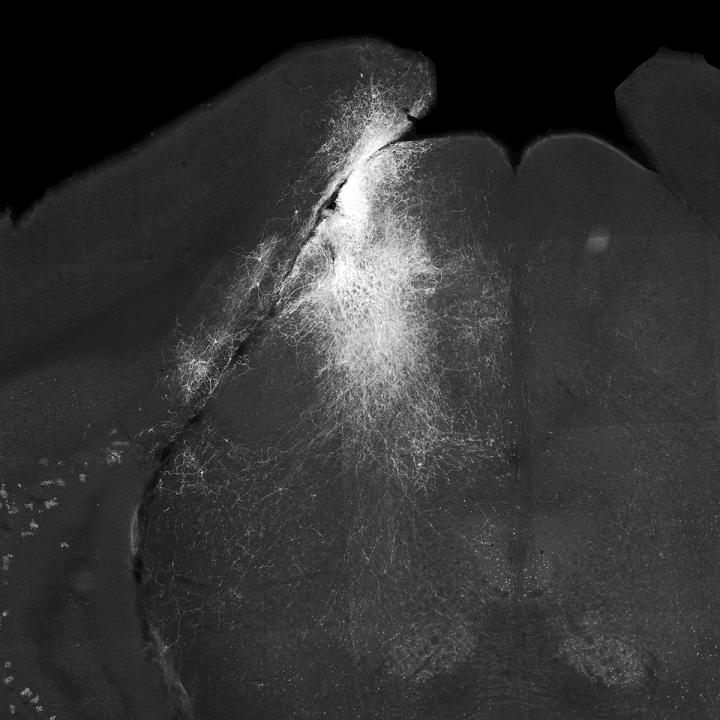

image: Slice of mouse brain showing neurons of the superior colliculus highlighted on one side.

Inhibiting the cells of the superior colliculus made the mice less likely to report that they'd seen an event, and when they did, their decision took longer. The inhibition had to occur within a 100 millisecond (one-tenth of a second) interval after the visual event. If the inhibition was outside that 100-millisecond timeframe, the mouse's decisions were mostly unaffected. The inhibition was side-specific: because the retinal cells cross over and connect to the superior colliculus on the opposite side of the head (the left eye is connected to the right superior colliculus and vice versa), inhibiting the right side of the superior colliculus depressed responses to stimuli on the left side, but not on the right.